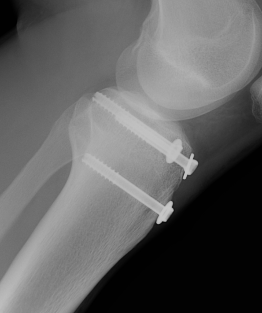

Type I /Type II

Technique

Screw +/- anchor fixation +/- tension band fixation of tibial tubercle and patella tendon

- screw +/- washer in fragment if large

- can supplement with Krackow sutures in patella tendon and fixed distally with suture anchors